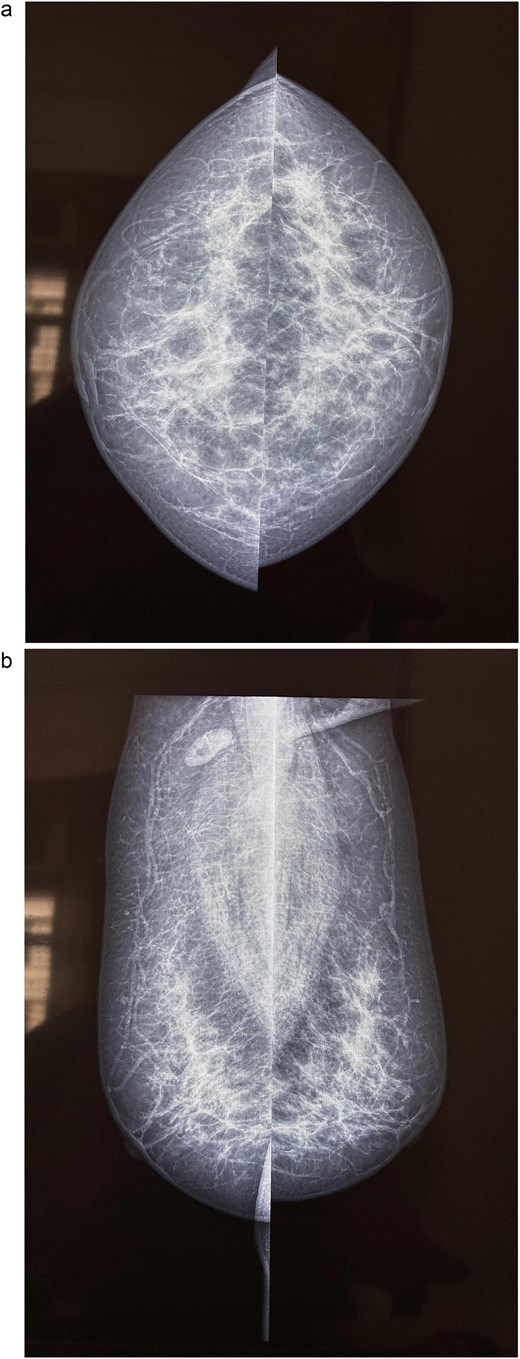

A 58-year-old woman with no relevant family history underwent routine health screening during which a left breast lump was detected. Mammography showed a high density spiculated lesion in the upper outer quadrant (BIRADS 4c/5) (Fig. 1a and b). Ultrasound demonstrated a 1.0 × 1.1 cm spiculated, heterogeneous hypoechoic lesion (BIRADS 4c). FDG positron emission tomography computed tomography (PET CT) revealed mild uptake confined to the breast lesion (SUVmax ~2.5) with no FDG avid axillary nodes or distant disease (Fig. 2a and b). Ultrasound guided FNAC revealed infiltrating ductal carcinoma (Yokohama Category 5) with cohesive clusters and scattered malignant ductal epithelial cells showing nuclear overlapping, moderate pleomorphism, conspicuous nucleoli, and moderate cytoplasm in a hemorrhagic background.

Mammography of the left breast. (a) Craniocaudal view showing a high density spiculated lesion in the upper outer quadrant, consistent with BIRADS 4c/5, suspicious for malignancy. (b) Mediolateral oblique view demonstrating the same spiculated, high density lesion in the upper outer quadrant, corresponding to the known carcinoma (BIRADS 4c/5).